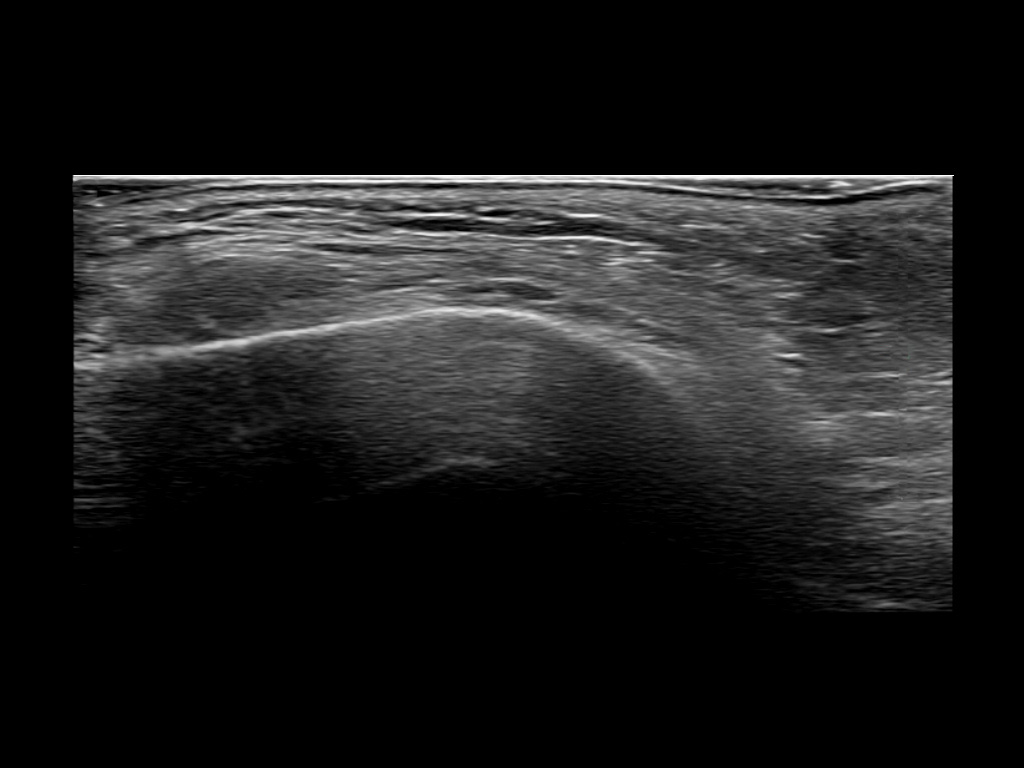

PCL 0

PCL 10a

PCL 11a

PCL 12a

PCL 13a

PCL 14a

PCL 15a

PCL 16a

PCL 1a

PCL 2a

PCL 3a

PCL 3b e

PCL 4a

PCL 4b e

PCL 5a

PCL 5b e